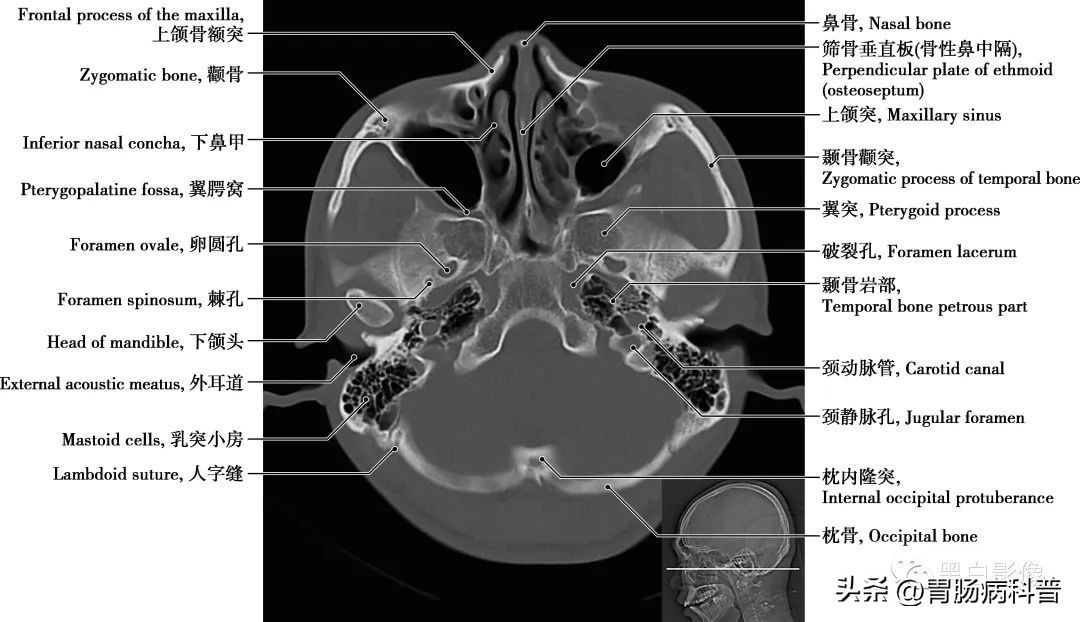

卵圆孔和棘孔 在蝶骨大翼近根部处由前向后可见圆孔、卵圆孔和棘孔,圆孔内走行上颌神经,卵圆孔内走行下颌神经,棘孔内走行脑膜中动脉。颈动脉管 是颈内动脉进入颅腔的管道,在颞骨岩部内弯曲形成一定角度,再经颈动脉管内口于破孔处离开颈动脉管进入颅内

图1-2-19 经小脑扁桃体轴位切面

上颌窦 上颌骨体内的锥形空腔,位于上颌骨体内,窦壁为骨质,窦壁覆黏膜,向内侧开口于中鼻道,分为一底、一尖及前、后、上、下四个壁。由于窦口高于窦底部,故在直立位时若有炎性物不易自然流出。鼻泪管 为一膜性管道,上部包埋在骨性鼻泪管中,与骨膜紧密相结合;下部在鼻腔外侧壁黏膜深面,下部开口于下鼻道外侧壁的前部

图1-2-20 经枕骨大孔轴位切面

翼突 为蝶骨一部分,从蝶骨体与蝶骨大翼连接处下垂,向后敞开成为内侧板和外侧板,根部贯通一矢状方向的细管,称翼管,向前通入翼腭窝。下鼻甲 有两块,呈卷曲样,形成鼻腔外侧壁的一部分。起到空气进入肺以前的循环及过滤作用